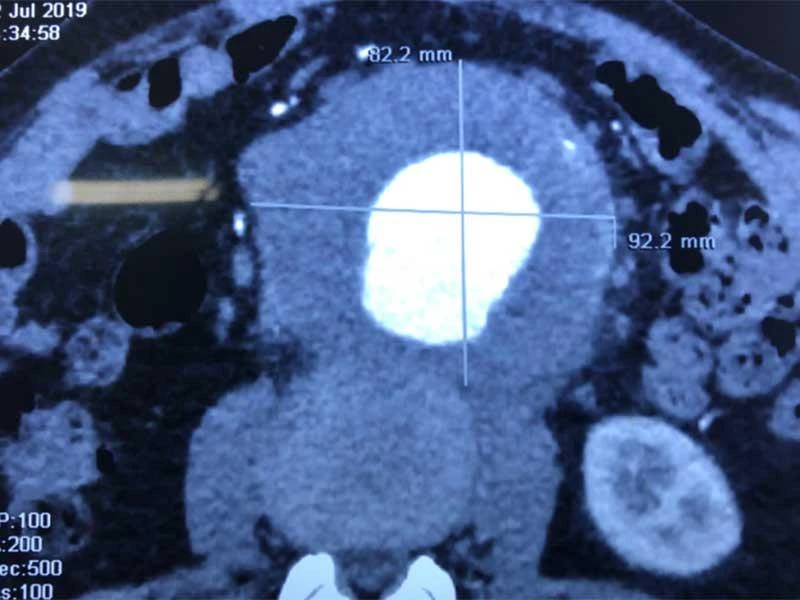

Tại đây, ông được chẩn đoán có túi phình kích thước 9 x 8,6 cm, như một trái bưởi nhỏ, nếu vỡ sẽ khiến một lượng lớn máu xòa ra trong ổ bụng, nguy cơ tử vong lên đến trên 90%. Sau hơn 2 giờ phẫu thuật, các bác sĩ đã loại bỏ trọn khối xơ vữa có trọng lượng 0,5 kg trong túi phình, đặt thành công ống ghép dacron (động mạch nhân tạo) vào động mạch chủ bụng thay thế cho đoạn bị phình giãn.

Hình ảnh siêu âm động mạch chủ bụng phình to như quả bưởi sắp vỡ của ông V.  Ảnh do BV Bình Dân cung cấp